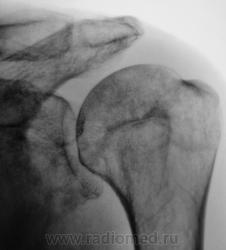

Валентин Львович, а с суставной впадиной лопатки все хорошо? У меня ее структура на подозрении...

Вы совершенно правы Татьяна Валентиновна. Я намеренно "обрезал" снимок, произведенный лаборантами, дабы акцентировать внимание на латеральном угле лопатки. Суставная поверхность лопатки и шейка внушают серьёзные подозрения, и с учетом "пороза" и структуры.

Снимок "без обрезания" - ниже. Врача-рентгенолога в кабинете не было, лаборанты, оценив его, начали "пытать" пациента. Оказалось, что флюорографию органов грудной полости, этот пациент, "проходил" лет 5 тому. Ну, и лаборанты приступили к стандартному исследованию органов грудной полости.